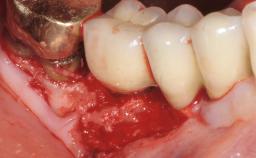

Resective Surgical Treatment of Peri-Implantitis Including Implantoplasty

In this case, Myroslav Solonko, Ignacio Sanz Sánchez and Mariano Sanz present a treatment that aims to eliminate exposed implant threads by modifying the implant surface, converting a moderately-rough surface into a smooth surface.

A 63-year-old male patient was referred to the post-graduate periodontal clinic of the Complutense University of Madrid for the treatment of peri-implantitis. According to the patient’s record, all his maxillary teeth had been extracted ten years previously due to severe periodontitis, and a full-mouth implant-supported restoration on eight implants was placed. No supportive periodontal therapy was provided apart from occasional check-ups by the restorative dentist.